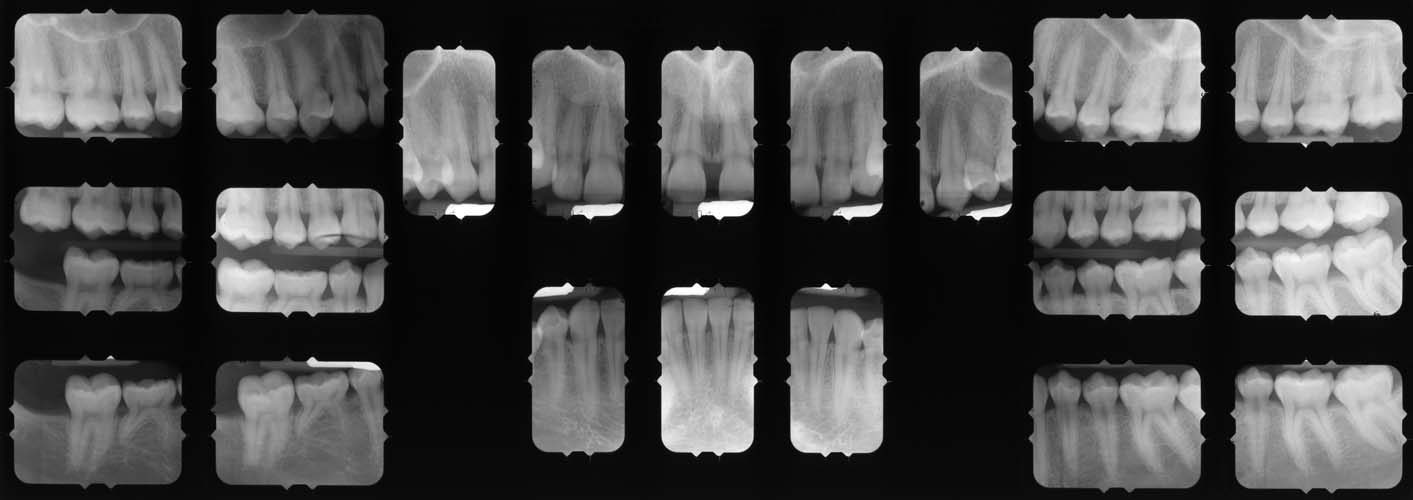

Question: S14 PM 27.7 Using the print of radiograph BMC40, answer the following question on the answer score sheet. (Select ONE OR MORE correct answers.) Which of the following is/are evident on the print of the radiograph?